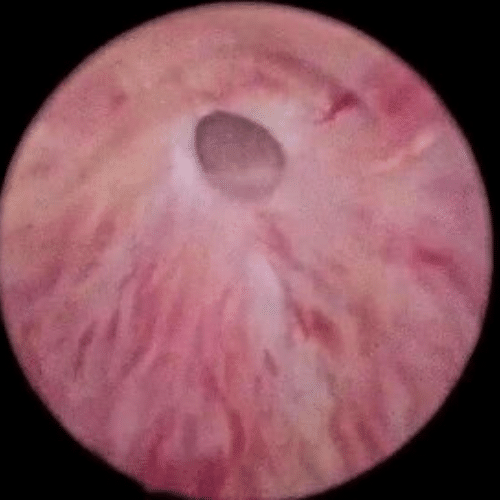

Imagen de uretrocistoscopía que muestra una estenosis uretral

Permite la evaluación de las características de la mucosa (la superficie de revestimiento) uretral y de la vejiga bajo visión directa. Complemento útil para una evaluación completa de la localización y severidad de la estenosis.